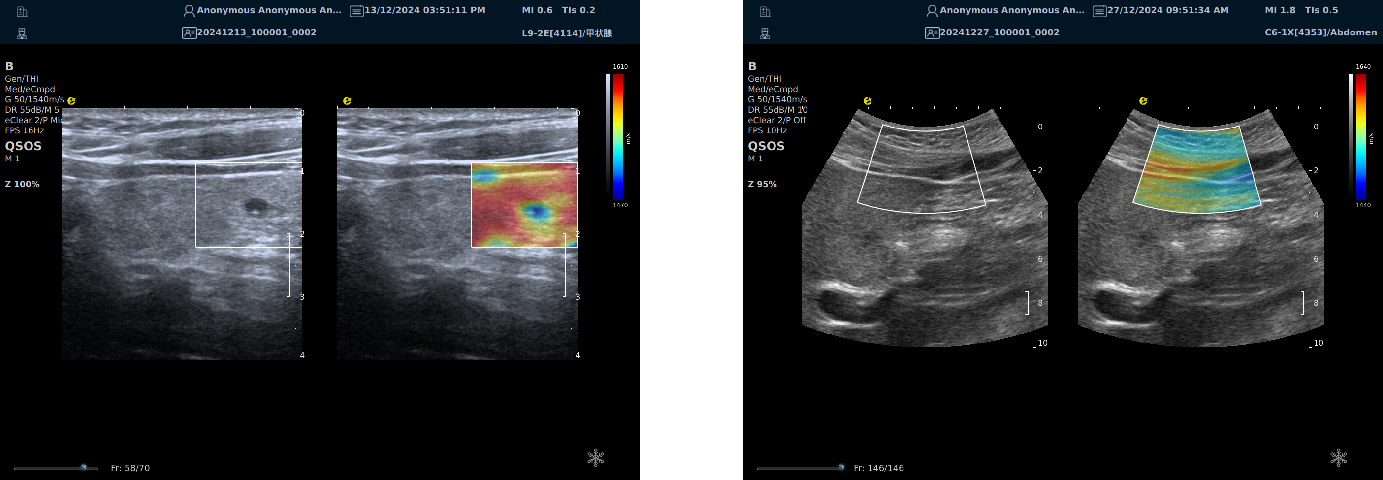

平面波超微细血流显像

能够提供更多真实的组织细小及末梢血管的血流信息,直观的观察组织内部的血管架构及血流形态的情况,提供临床更多有价值的诊断信息。

临床应用:

肿瘤鉴别诊断(肝脏、肾脏、甲状腺、乳腺、  涎腺等)

淋巴结评价(炎症、肿瘤)

肌骨系统临床诊断和疗效监测(关节、滑膜、韧带、肌肉炎症、 损伤等)

斑块内新生血管评估

超声介入术前进针方案提供血流参考信息

超声介入术后疗效评估

image.png